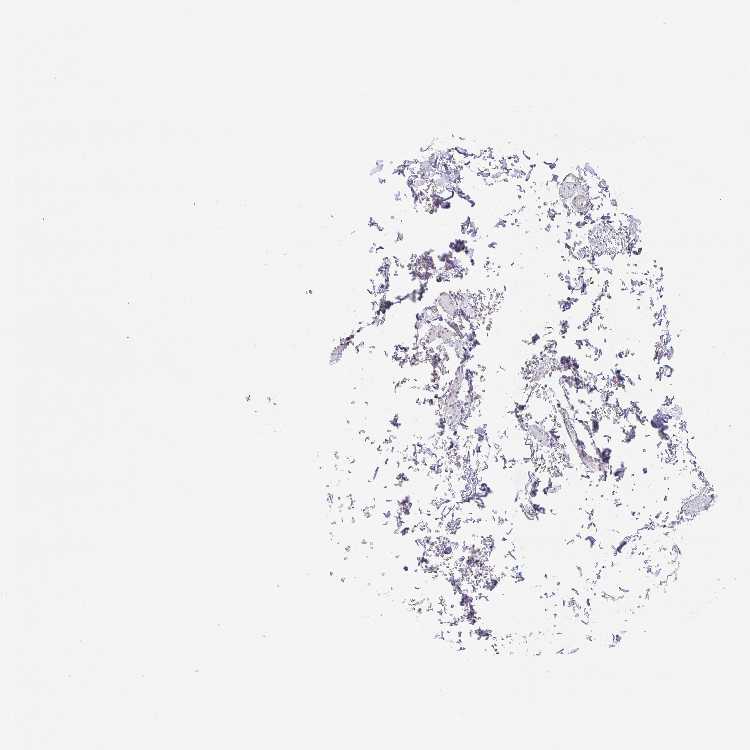

SOFT TISSUE 2 - Antibody stainingi

Antibody staining in the annotated cell types in the current human tissue is reported as not detected, low, medium, or high, based on conventional immunohistochemistry profiling in selected tissues. This score is based on the combination of the staining intensity and fraction of stained cells.

Each image is clickable and will lead to virtual microscopy that enables deeper exploration of all samples and also displays staining intensity scores, fraction scores and subcellular localization as well as patient and tissue information for each sample.

Antibody HPA019652

Fibroblasts Not detected

Peripheral nerve Not detected